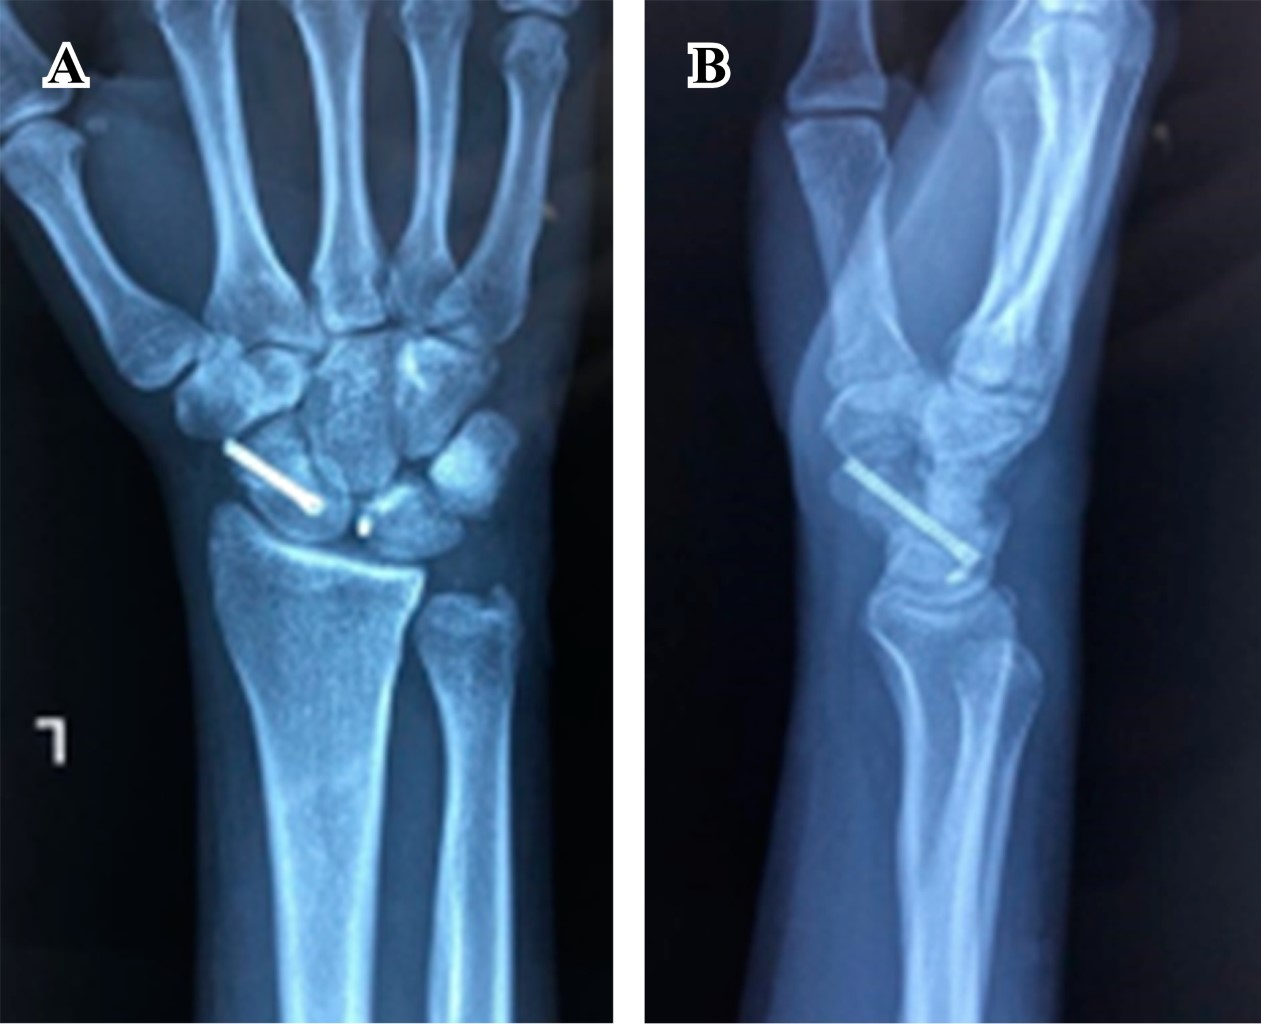

Una hora después de su ingreso, bajo previo consentimiento del paciente, en un primer tiempo se realiza reducción cerrada de la luxación del carpo mediante la maniobra de Tavernier con control fluoroscópico y bajo anestesia general, logrando adecuada reducción de la luxación. (Figura 3) Posteriormente se coloca una férula tipo pinza de azúcar y se decide programar en un segundo tiempo la reducción y osteosíntesis del escafoides debido al importante edema en dicha mano.

Figura 3